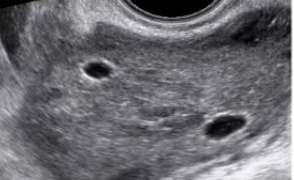

Leggi di piùCari colleghi, vi presentiamo la guida al counseling di Marzo 2025 sulla PCOS!! Potrete scaricarla cliccando sul link. Grazie a Mara Albanese! ...